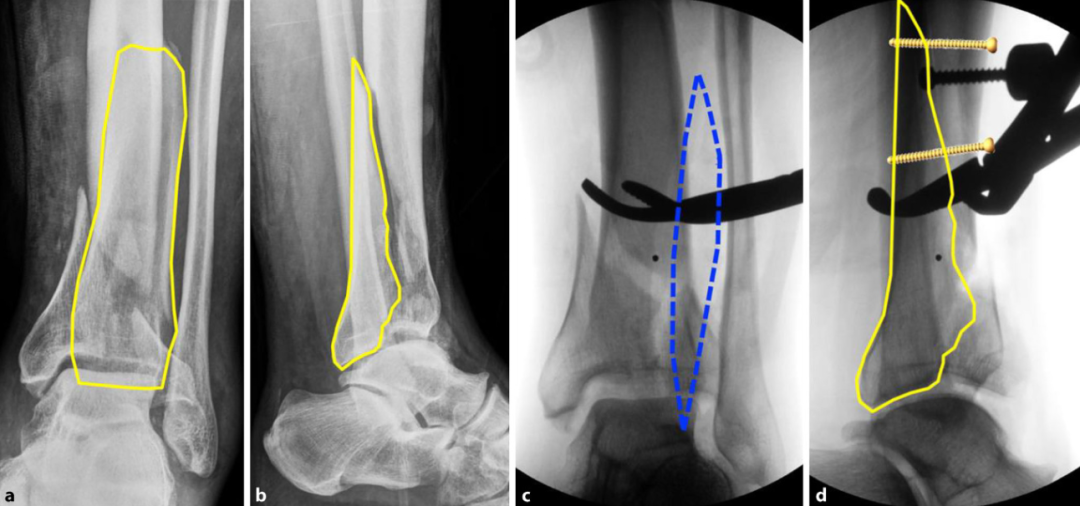

图a、b.术前X线显示Pilon骨折(AO 43-C3 型)。一个较大的后侧关节骨折块(黄色轮廓标注)可简单延伸至骨干区域;c、d. 通过前外侧入路(c,蓝色虚线标注),使用复位钳将后侧关节骨折块(d,黄色轮廓标注)解剖复位到骨干上,并用2枚螺钉固定。通过这一操作,将C型骨折转化为B型骨折。